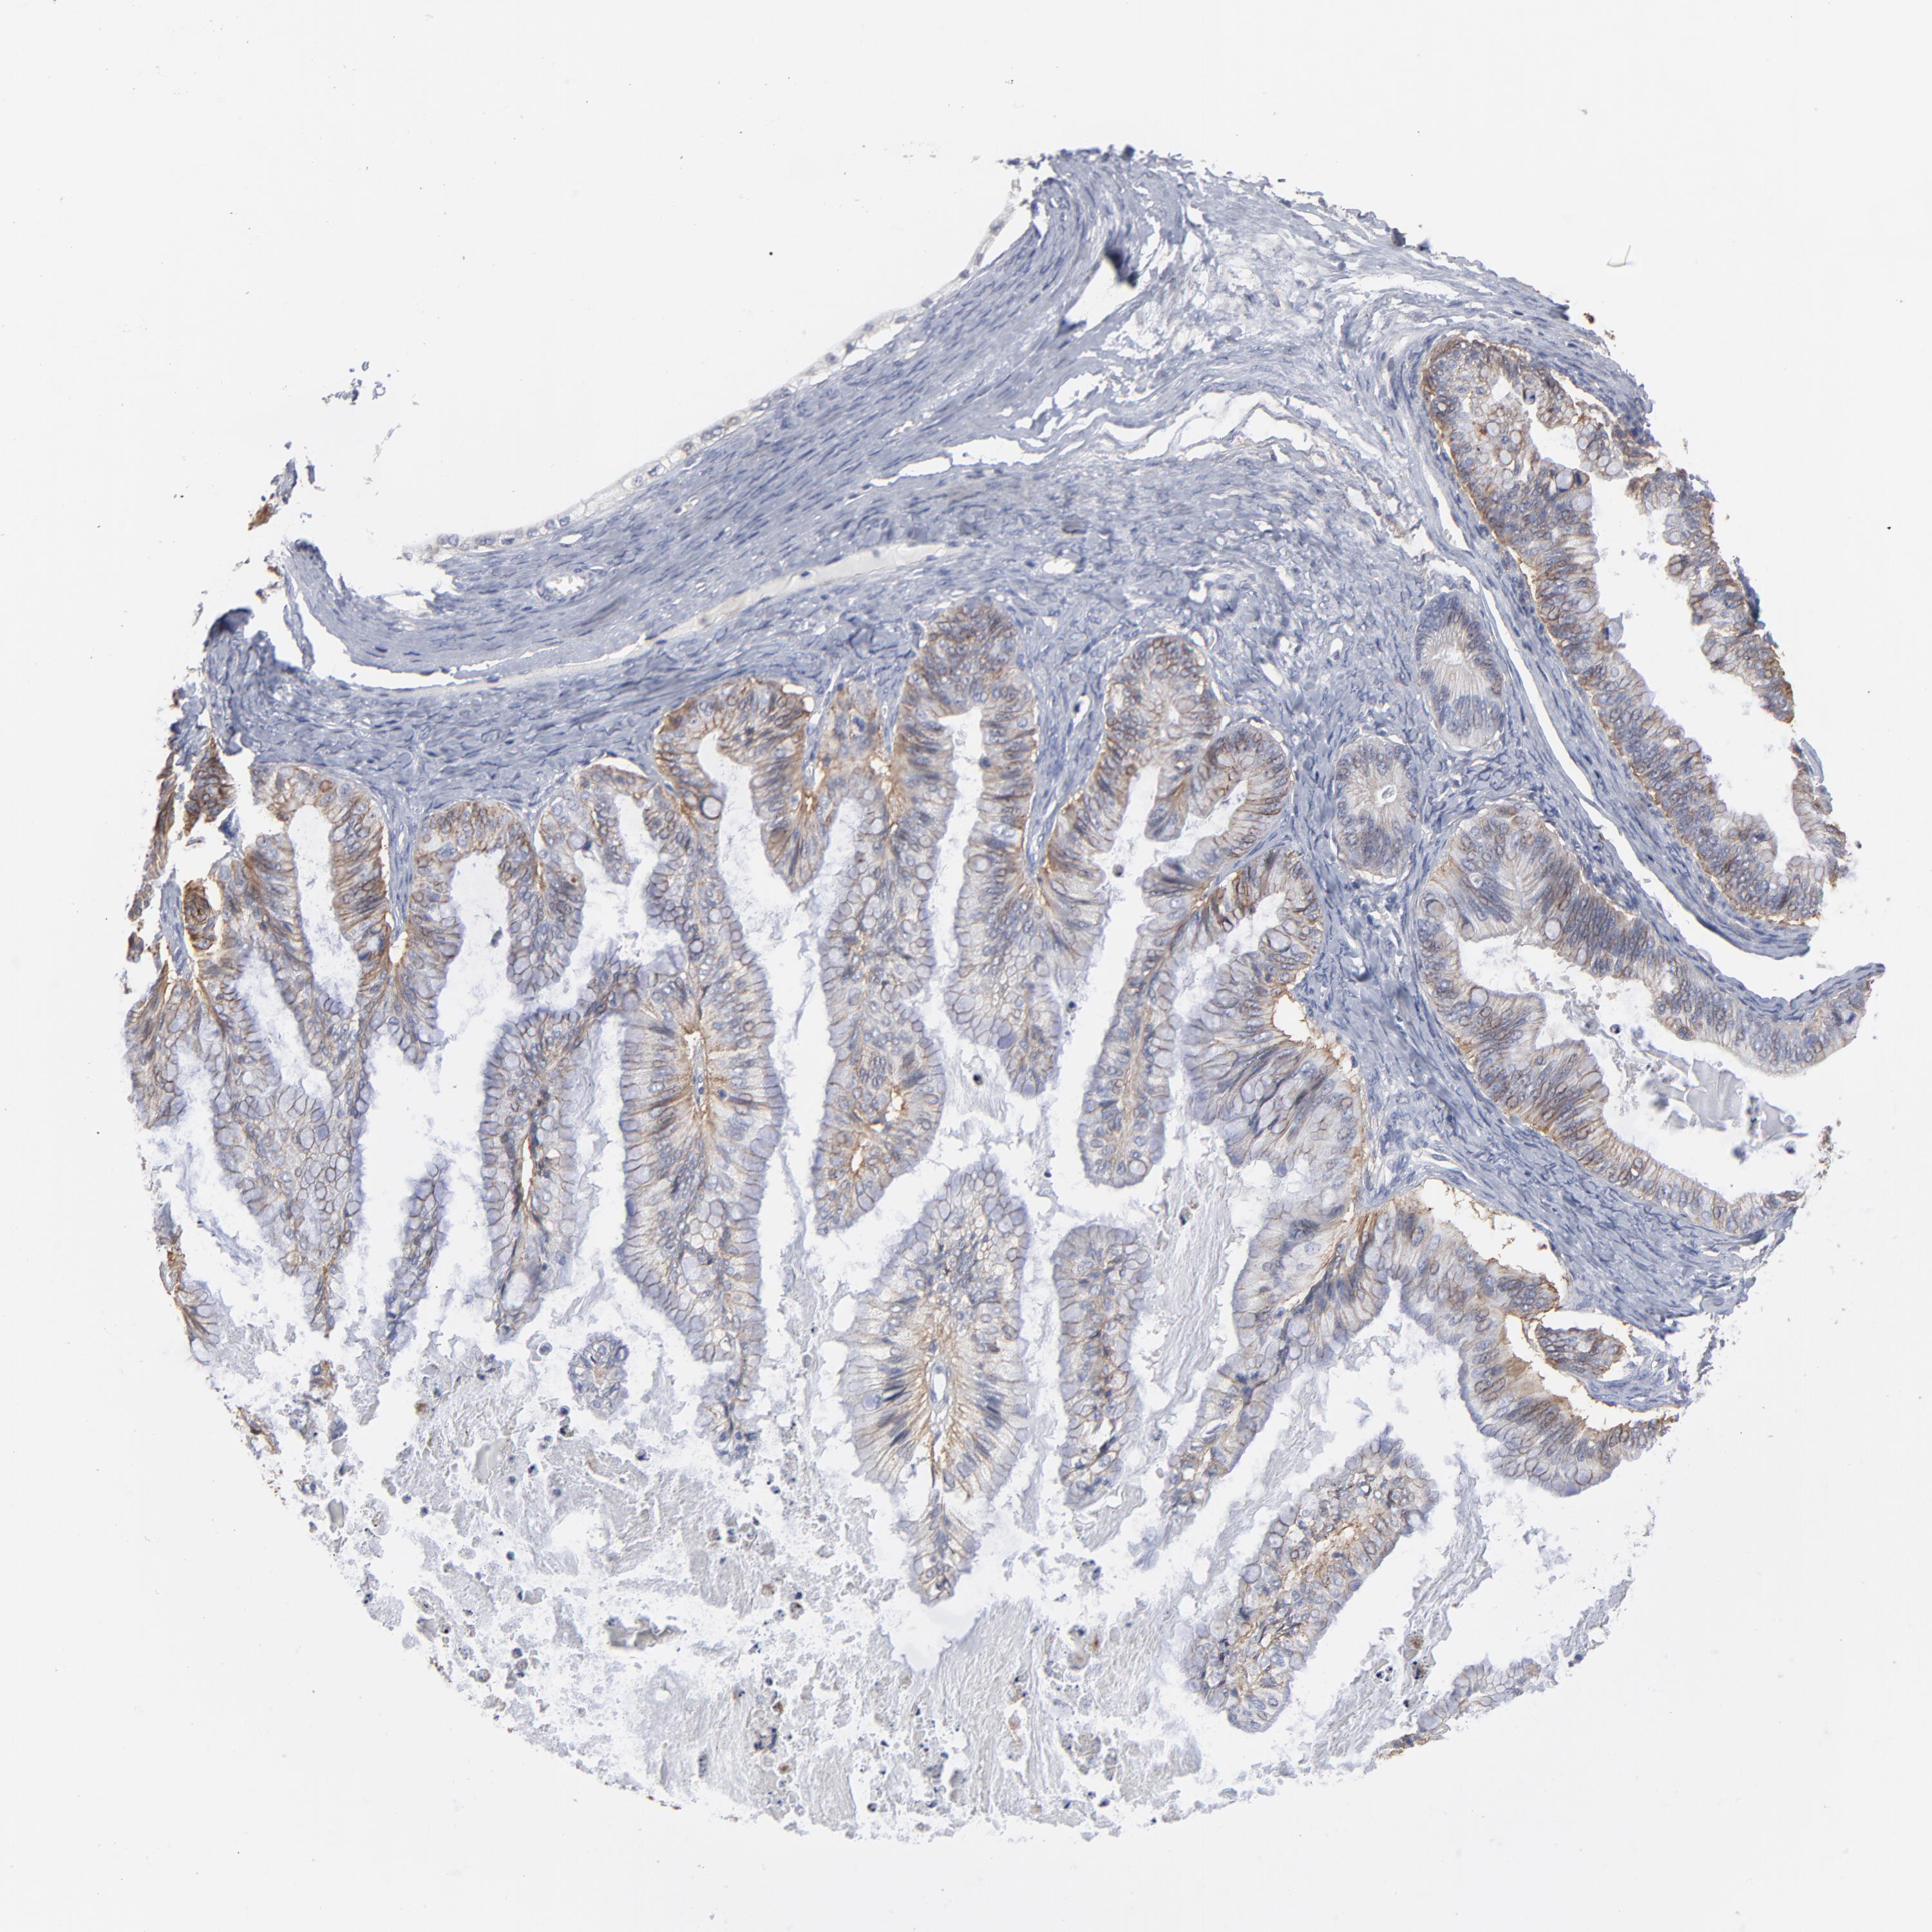

OVARIAN CANCER - Protein expressioni

A mouse-over function shows sample information and annotation data. Click on an image to view it in a full screen mode. Samples can be filtered based on level of antibody staining by selecting one or several of the following categories: high, medium, low and not detected. The assay and annotation is described here.

Note that samples used for immunohistochemistry by the Human Protein Atlas do not correspond to samples in the TCGA dataset.

Antibody stainingi

Antibody staining in the annotated cell types in the current human tissue is reported as not detected, low, medium, or high, based on conventional immunohistochemistry profiling in selected tissues. This score is based on the combination of the staining intensity and fraction of stained cells.

Each image is clickable and will lead to virtual microscopy that enables deeper exploration of all samples and also displays staining intensity scores, fraction scores and subcellular localization as well as patient and tissue information for each sample.

Antibody HPA003324

Staining

High

Medium

Low

Not detected

Intensity

Strong

Moderate

Weak

Negative

Quantity

>75%

75%-25%

<25%

None

Location

Nuclear

Cytoplasmic/membranous

Cytoplasmic/membranous,nuclear

Cystadenocarcinoma, mucinous, NOS

Carcinoma, endometroid

Cystadenocarcinoma, serous, NOS